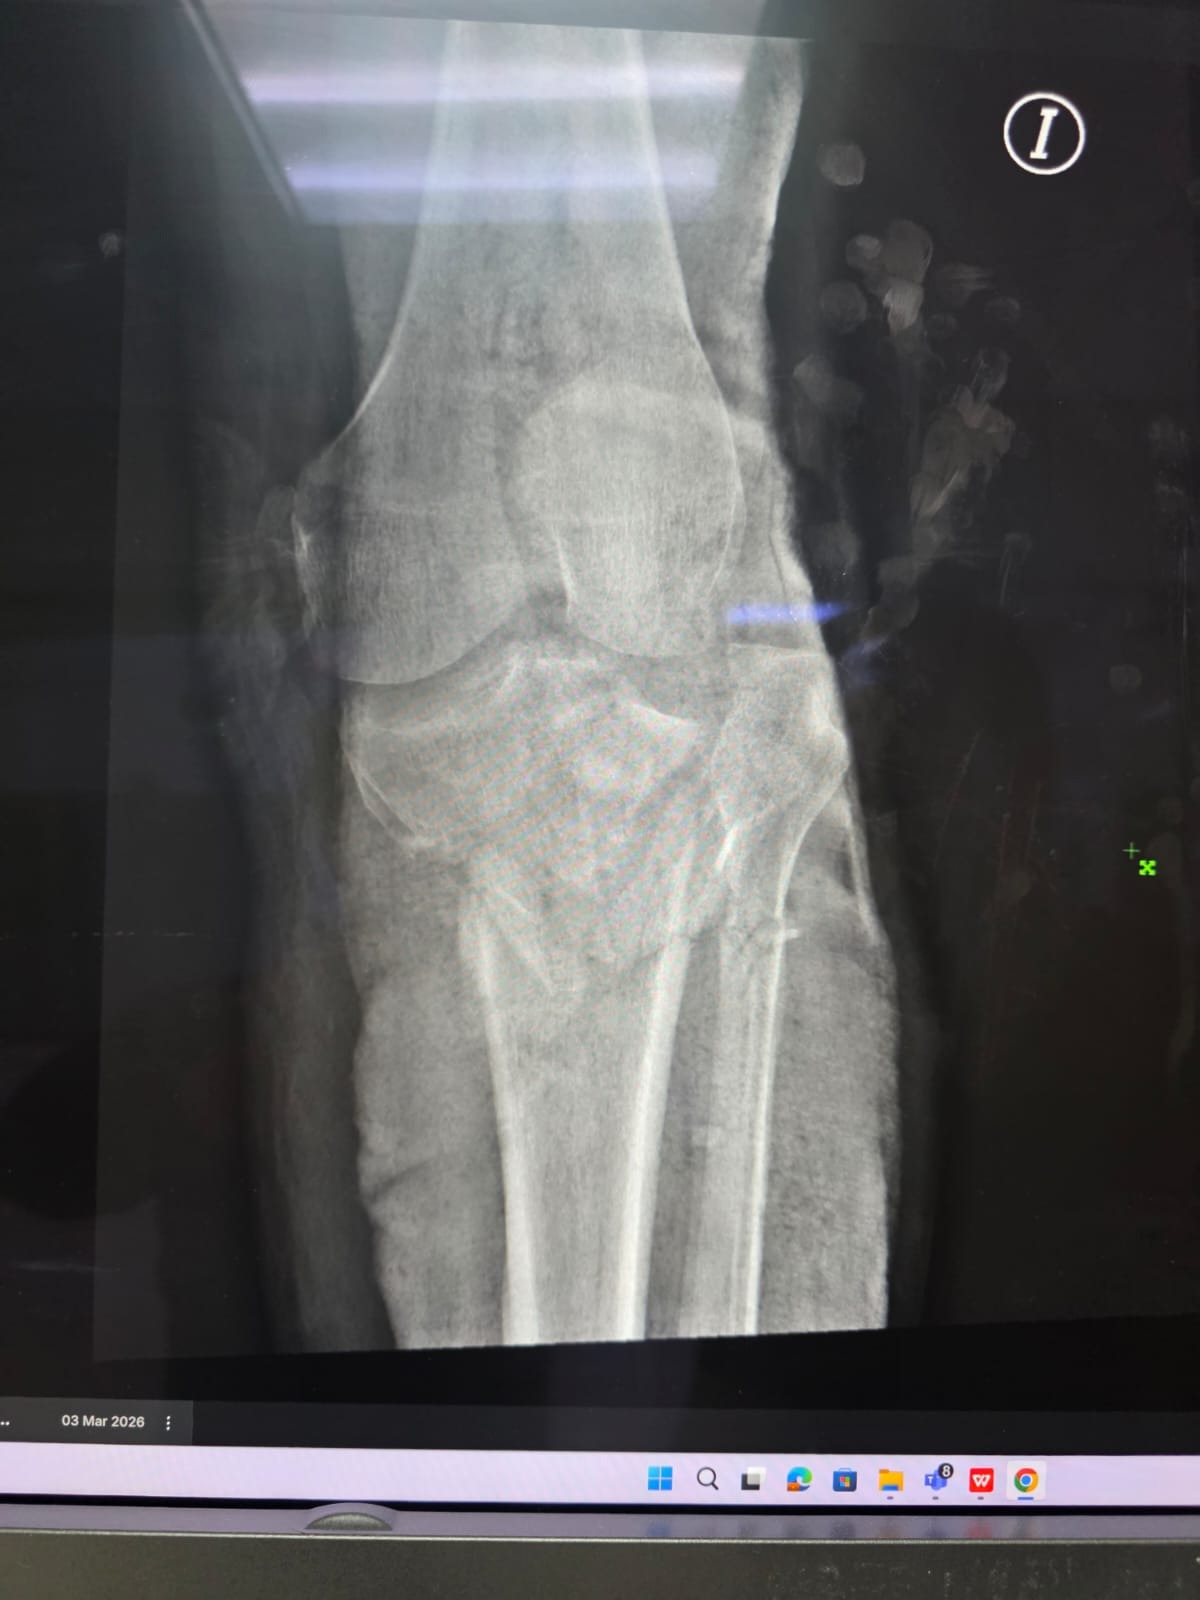

El pasado 2 de marzo, fui atropellado por una persona que huyó del lugar sin hacerse responsable. El accidente me dejó con lesiones importantes en mi pierna y rodilla, por lo que actualmente me encuentro hospitalizado y enfrentaré un proceso largo de recuperación, incluyendo cirugía y rehabilitación.

Debido a que el vehículo me arrastró, también sufrí laceraciones en la pierna, por lo que los médicos han tenido que posponer la operación hasta que las heridas cicatricen, lo que hace que el proceso sea más largo y complicado.